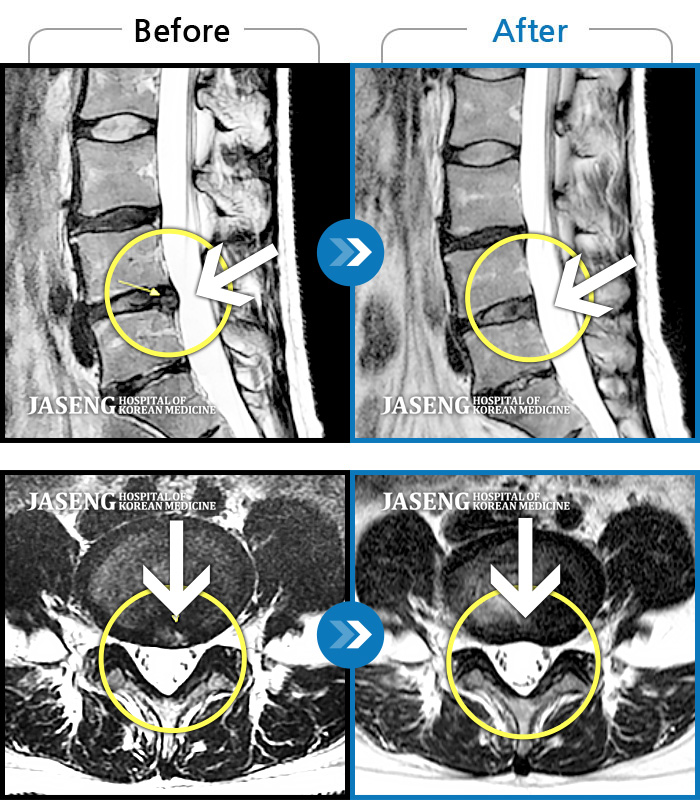

MRI 치료사례

허리통증, 왼쪽 다리 저림 및 통증